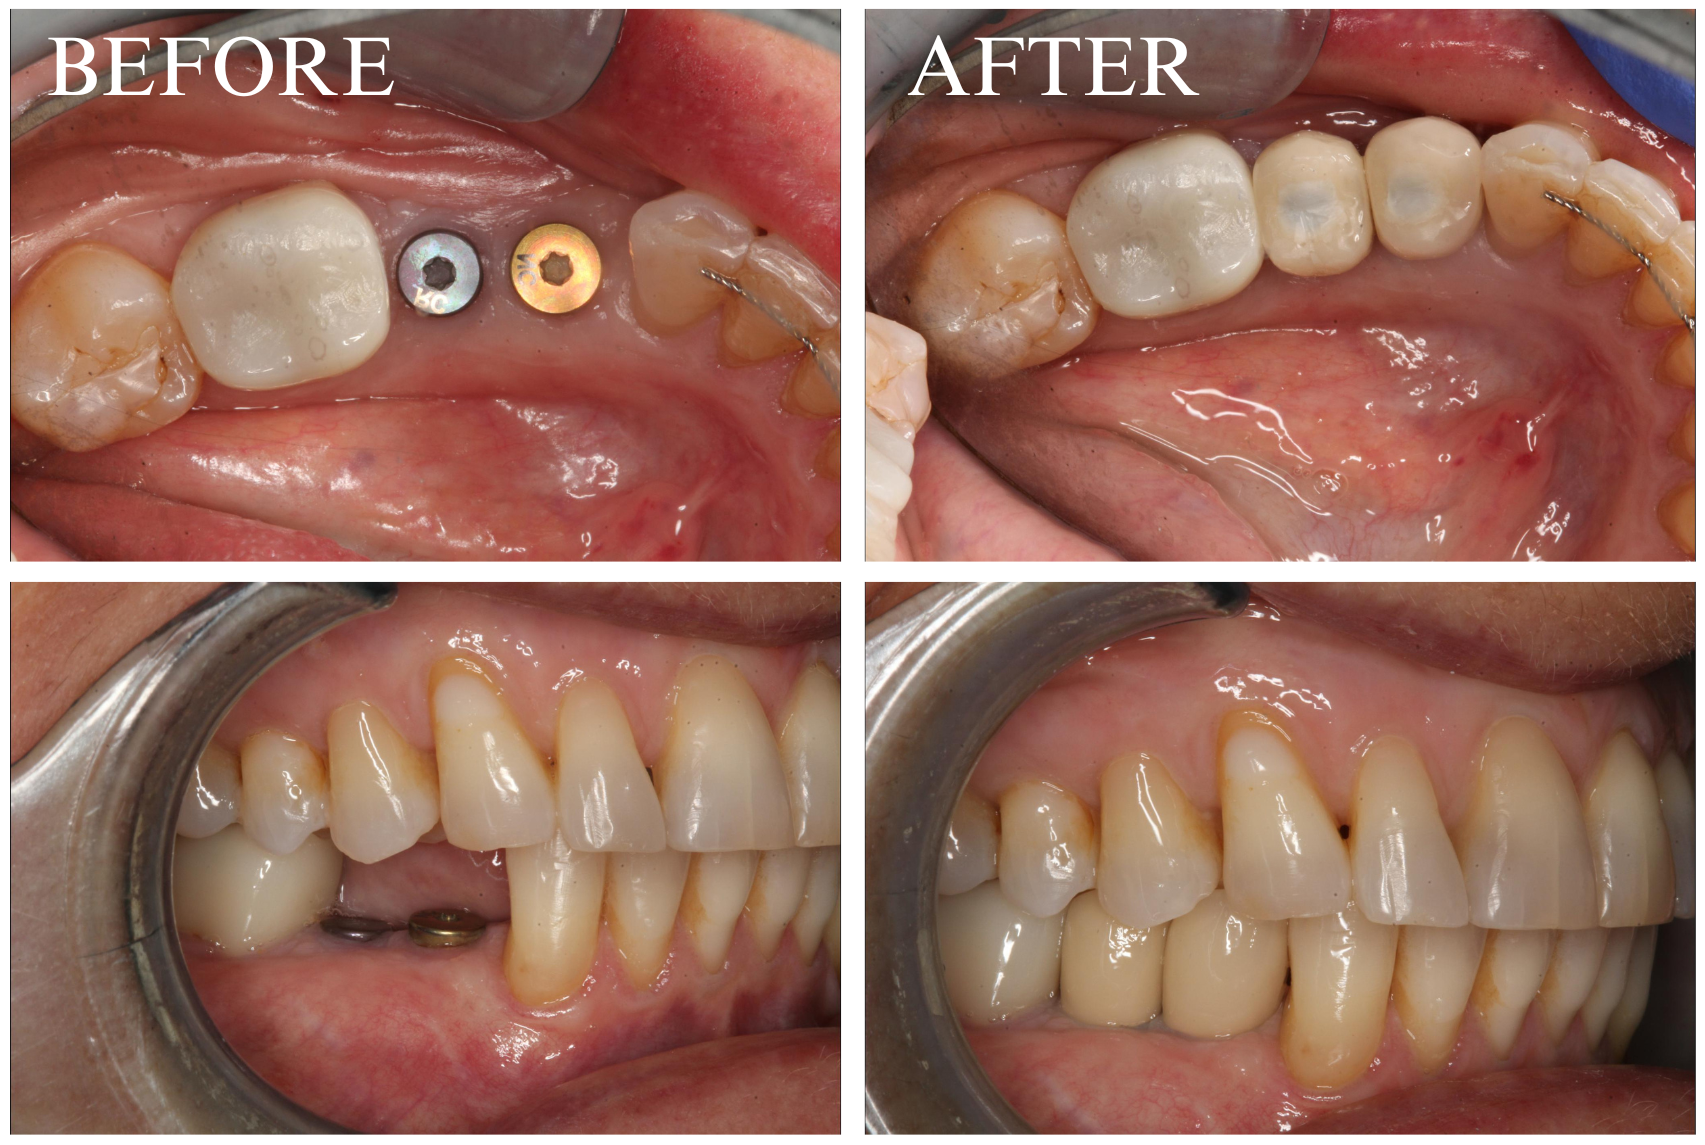

Dental implants provide a strong, long-lasting foundation for replacement teeth that look, feel, and function like natural teeth.

As Dr. Lopez-Belio always says, implants are a “one-tooth solution for a one-tooth problem.” Titanium implants are surgically placed into the jawbone where teeth are missing. Over time, the bone integrates with the implant, creating a foundation for the porcelain restoration. This process prevents bone loss, which naturally occurs when teeth are missing.

Photo Gallery

Lower First Molar